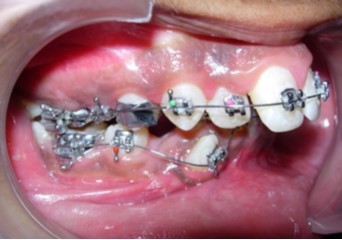

Intraoral assessment. (Figure 1d,Figure 1e,Figure 1f,Figure 1g,Figure 1h).

The maxillary arch was V-shaped with severely proclined and rotated maxillary incisors with a palatally placed 12. The mandibular arch was U-shaped with severe crowding of mandibular incisors, with 43 partially erupted and buccally placed with transpositioned 42 and 43, with 42 mesiolingually rotated, 33 distolingually rotated and 34 distolingually rotated and buccally placed.

Severe increase in overjet and deep bite were both observed. The maxillary midline coincided with the skeletal midline but the mandibular midline was shifted to the right side by 1 mm. Bilateral maxillary posterior crossbite was also observed. On right side the molar relation was Class I and on the left side it was Class II. The canine relation was Class II on the left side and the curve of Spee was increased.